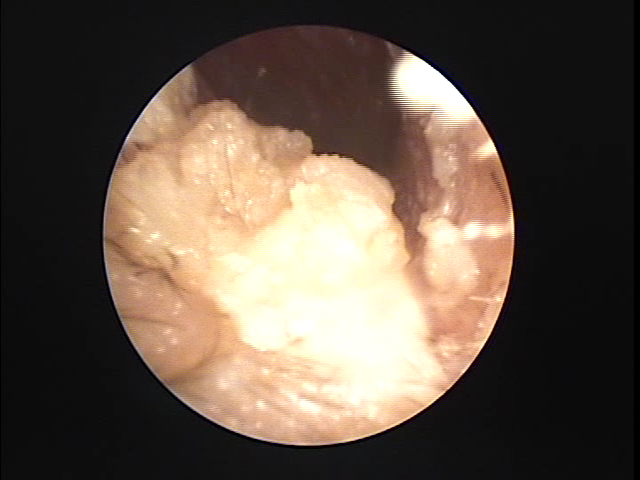

鉗子で

左耳の耳垢そうじ 福岡市博多区

耳用の特殊な鉗子で耳あかをつかんで取り出しています。